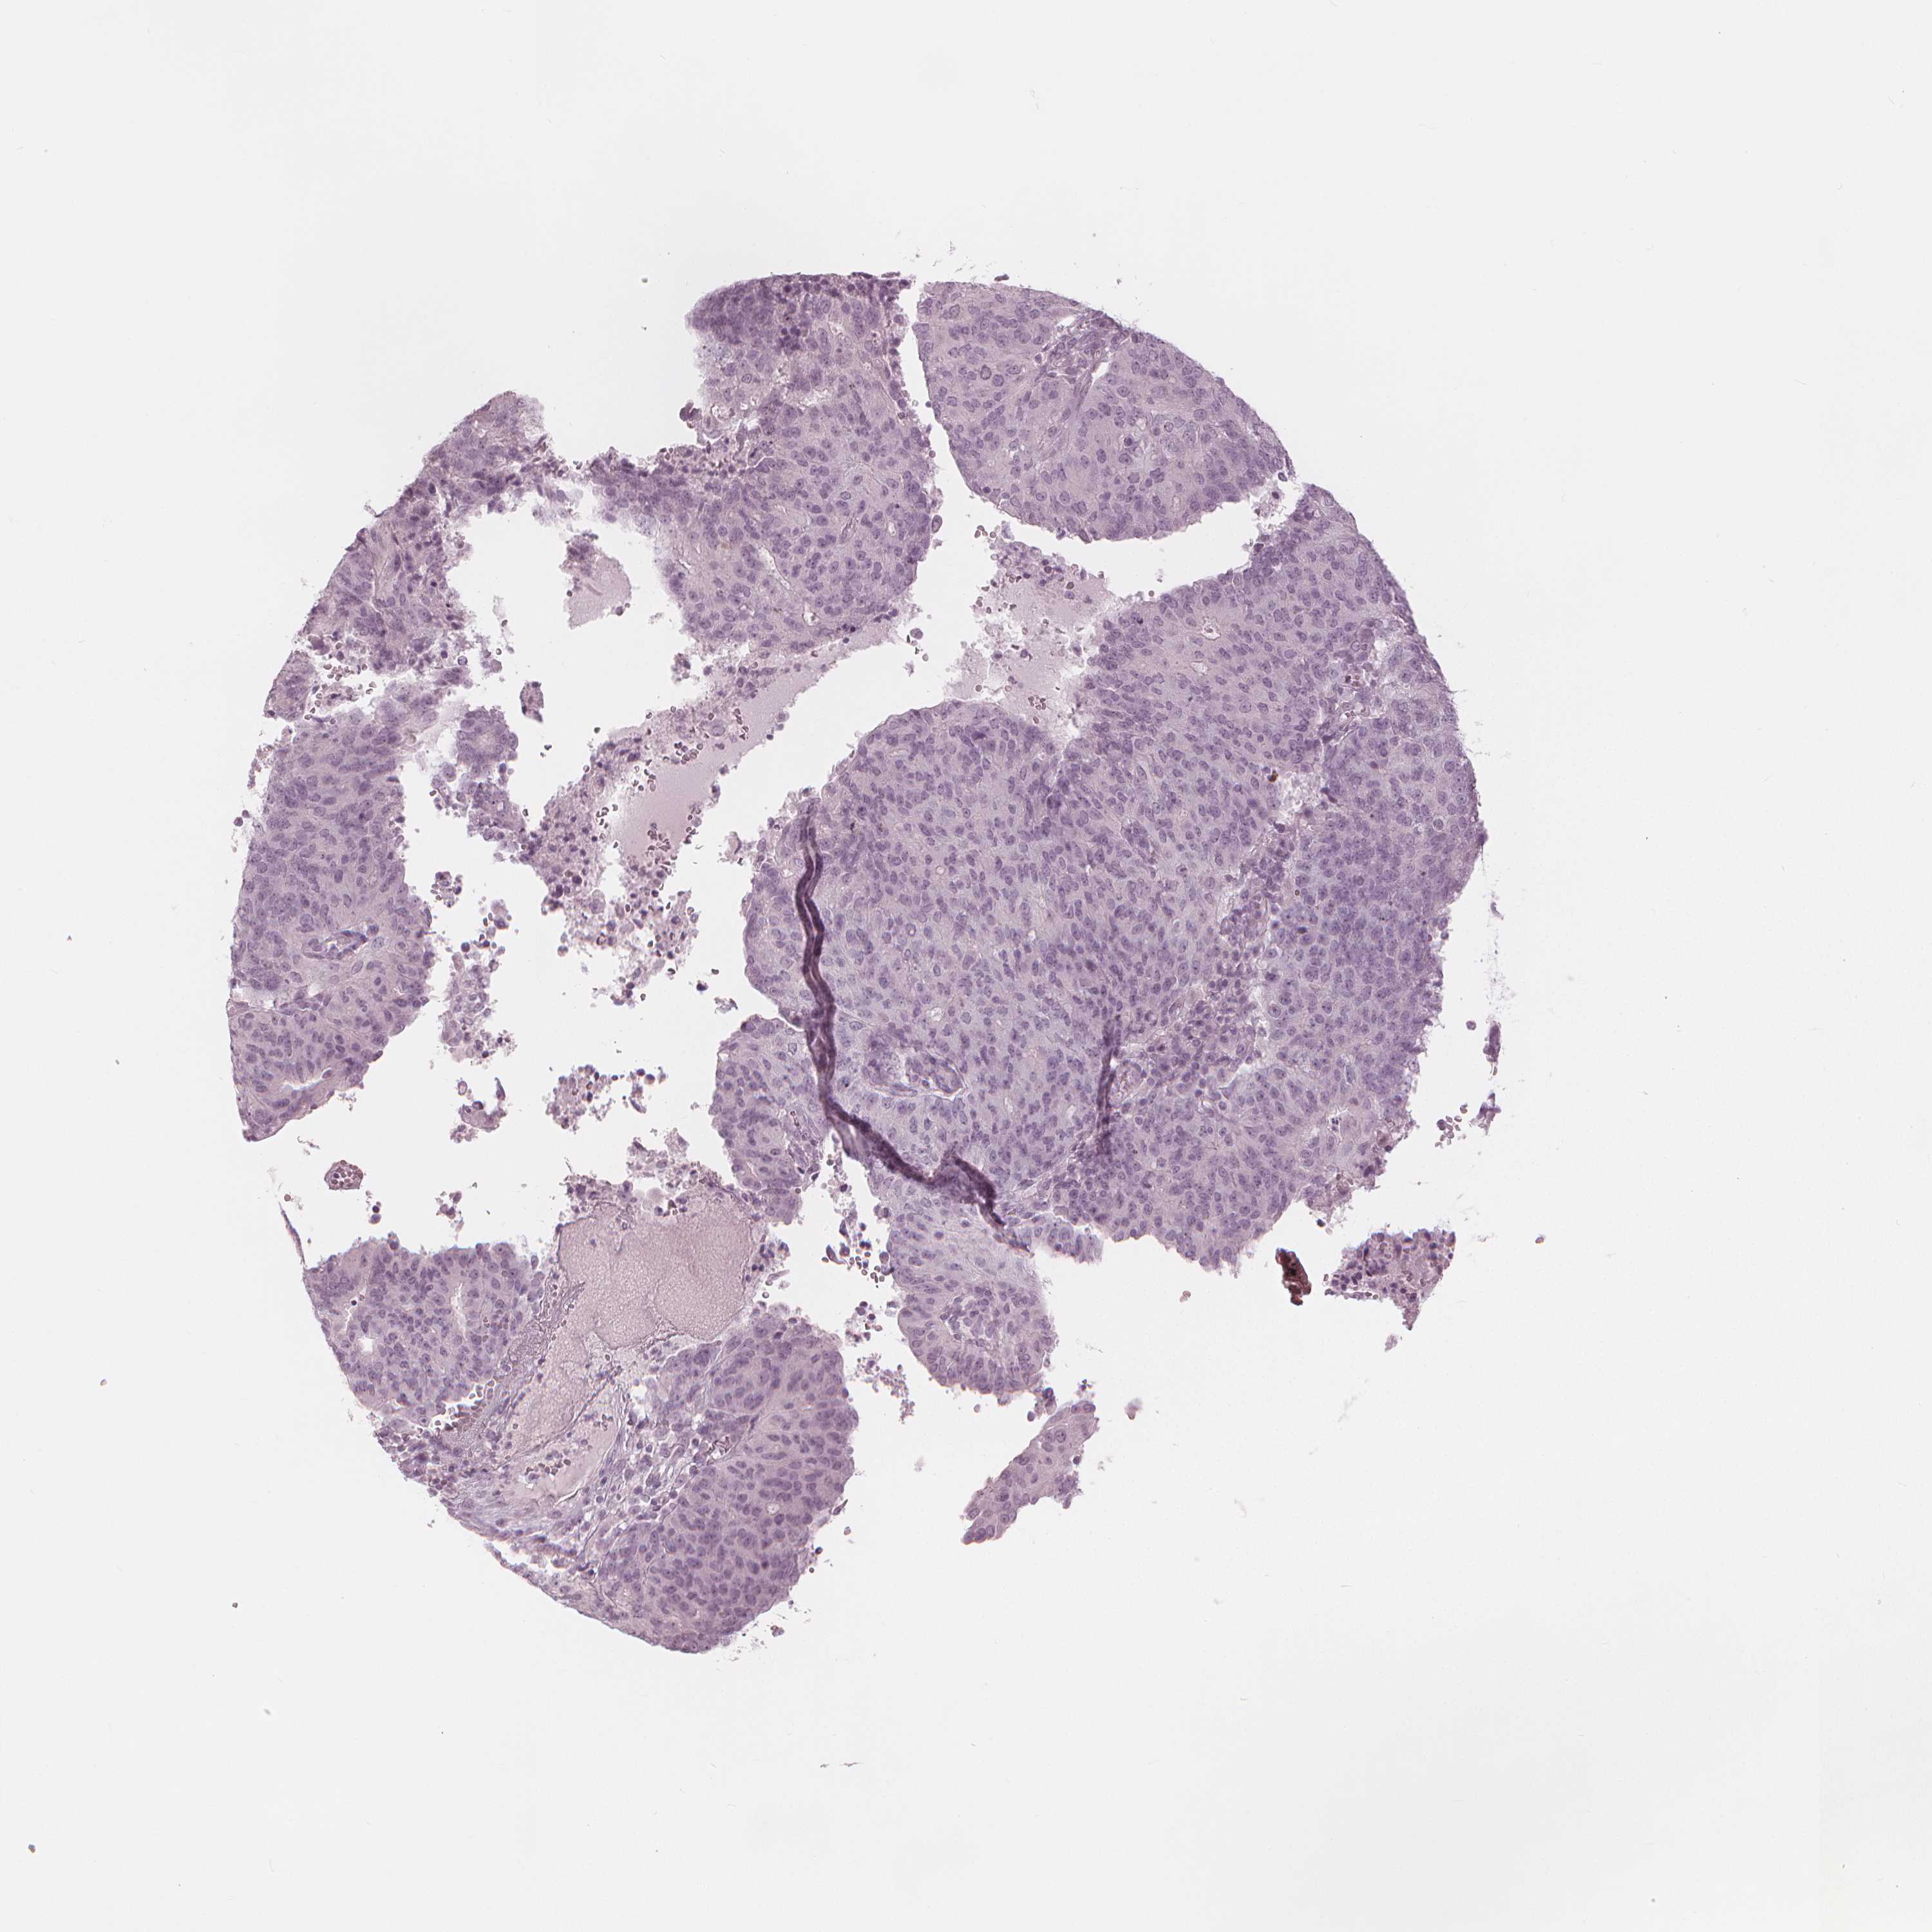

ENDOMETRIAL CANCER - Protein expressioni

A mouse-over function shows sample information and annotation data. Click on an image to view it in a full screen mode. Samples can be filtered based on level of antibody staining by selecting one or several of the following categories: high, medium, low and not detected. The assay and annotation is described here.

Note that samples used for immunohistochemistry by the Human Protein Atlas do not correspond to samples in the TCGA dataset.

Antibody stainingi

Antibody staining in the annotated cell types in the current human tissue is reported as not detected, low, medium, or high, based on conventional immunohistochemistry profiling in selected tissues. This score is based on the combination of the staining intensity and fraction of stained cells.

Each image is clickable and will lead to virtual microscopy that enables deeper exploration of all samples and also displays staining intensity scores, fraction scores and subcellular localization as well as patient and tissue information for each sample.

Antibody HPA020108

Antibody HPA029473

Antibody CAB016762

Staining

High

Medium

Low

Not detected

Intensity

Strong

Moderate

Weak

Negative

Quantity

>75%

75%-25%

<25%

None

Location

Nuclear

Cytoplasmic/membranous

Cytoplasmic/membranous,nuclear

Adenocarcinoma, NOS

Adenocarcinoma, metastatic, NOS

Carcinoma, NOS